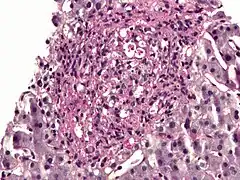

PAS diastase showing Histoplasma in a liver biopsy.

Periodic acid–Schiff–diastase (PAS-D, PAS diastase) stain is a periodic acid–Schiff (PAS) stain used in combination with diastase, an enzyme that breaks down glycogen. PAS-D is a stain often used by pathologists as an ancillary study in making a histologic diagnosis on paraffin-embedded tissue specimens. PAS stain typically gives a magenta color in the presence of glycogen. When PAS and diastase are used together, a light pink color replaces the deep magenta. Differences in the intensities of the two stains (PAS and PAS-D) can be attributed to different glycogen concentrations and can be used to semiquantify glycogen in samples. In practice, the tissue is deparaffinized, the diastase incubates, and then the PAS stain is applied.

An example of PAS-D in use is in showing gastric/duodenal metaplasia in duodenal adenomas.[1] PAS diastase stain is also used to identify alpha-1 antitrypsin globules in hepatocytes, which is a characteristic finding of alpha-1 antitrypsin deficiency.[2] PAS diastase stain is also used in diagnosing Whipple’s disease, as the foamy macrophages that infiltrate the lamina propria of the small intestine in this disease possess PAS-positive, diastase-resistant inclusions.[3]